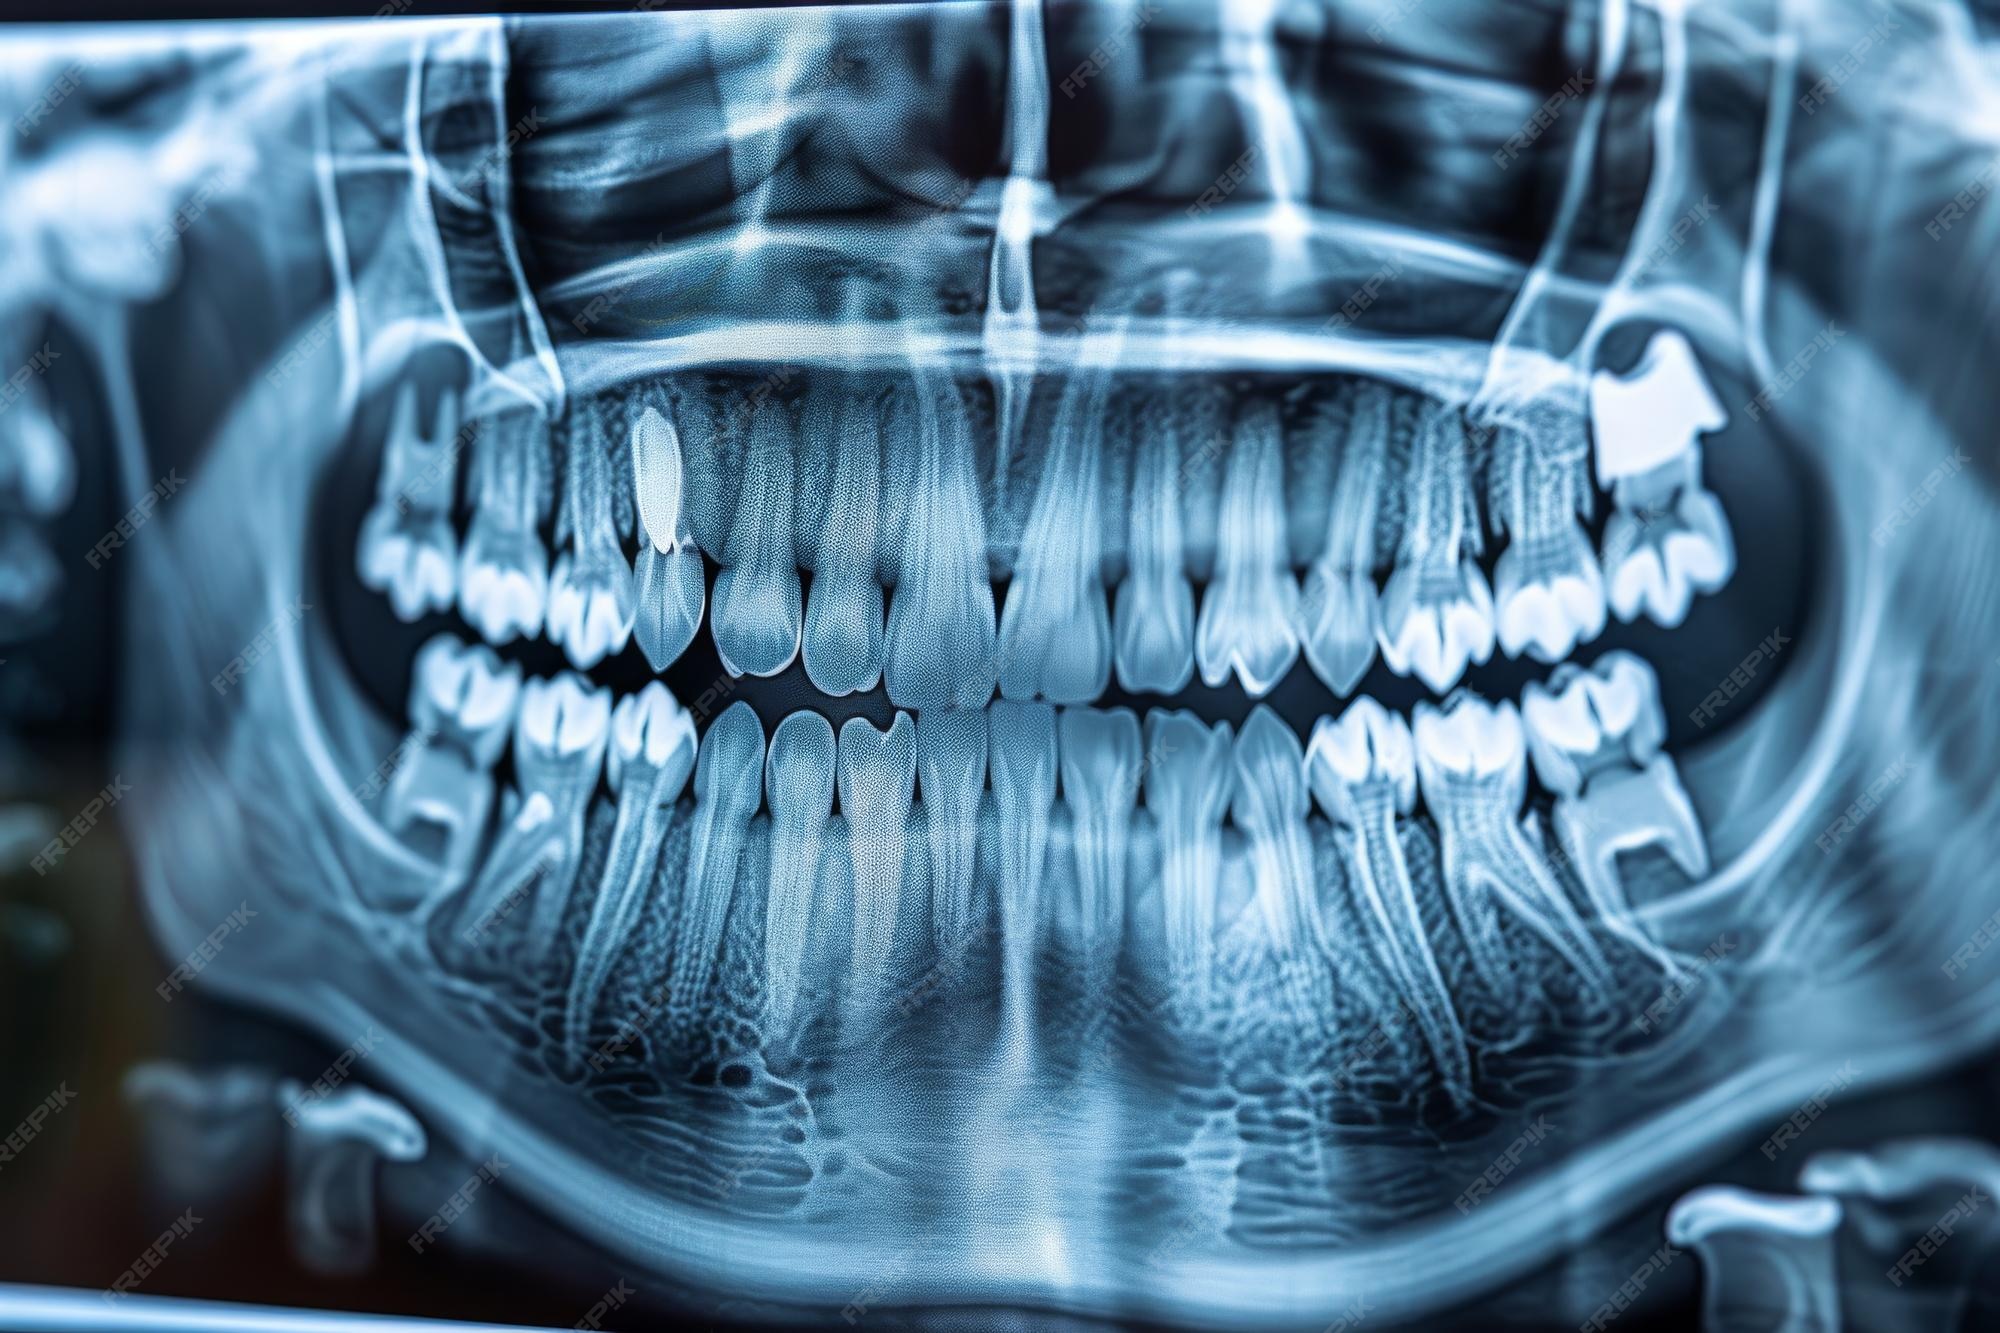

Dentists use advanced imaging to monitor the position and health of your 3rd molar teeth. During a routine exam, a panoramic X-ray is typically taken. This image provides a complete view of the upper and lower jaws, allowing the dentist to observe the angle of the teeth, their proximity to nerves, and whether they are likely to interfere with the alignment of your existing healthy teeth.